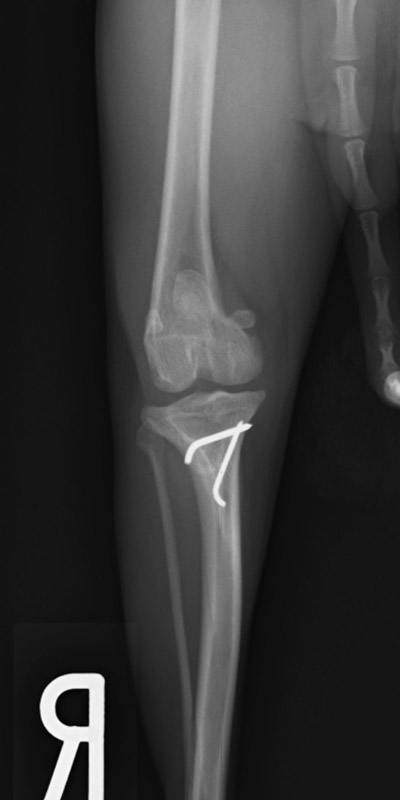

肘関節内骨折

アメリカン・コッカー・スパニエル(5歳)

車の窓から落下

手術前

手術後